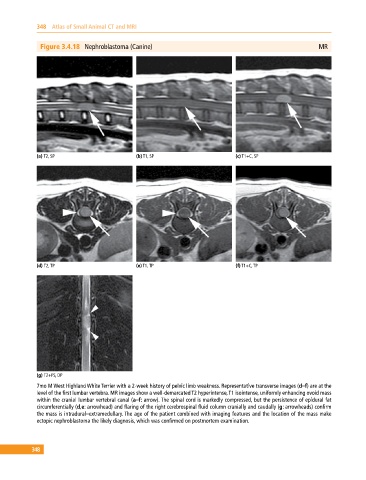

Figure 3.4.18 Nephroblastoma (Canine) MR

(a) T2, SP (b) T1, SP (c) T1+C, SP

(d) T2, TP (e) T1, TP (f) T1+C, TP

(g) T2+FS, DP

7mo M West Highland White Terrier with a 2‐week history of pelvic limb weakness. Representative transverse images (d–f) are at the

level of the first lumbar vertebra. MR images show a well‐demarcated T2 hyperintense, T1 isointense, uniformly enhancing ovoid mass

within the cranial lumbar vertebral canal (a–f: arrow). The spinal cord is markedly compressed, but the persistence of epidural fat

circumferentially (d,e: arrowhead) and flaring of the right cerebrospinal fluid column cranially and caudally (g: arrowheads) confirm

the mass is intradural–extramedullary. The age of the patient combined with imaging features and the location of the mass make

ectopic nephroblastoma the likely diagnosis, which was confirmed on postmortem examination.